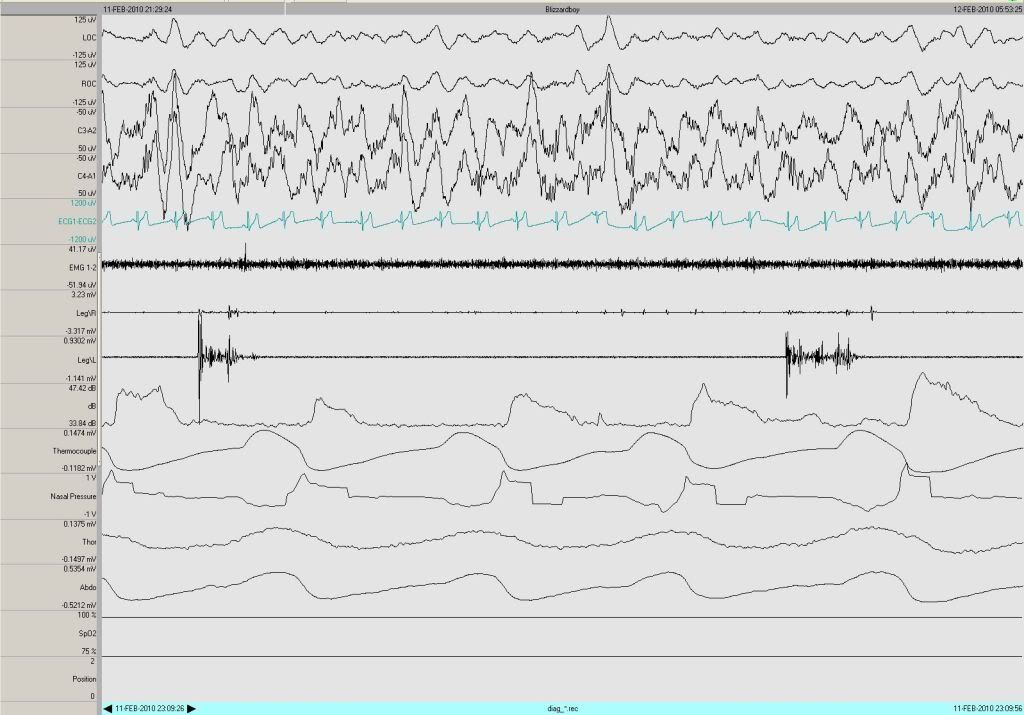

Speaking of which, in the very next epoch, two PLMs being slept through nicely.jnk wrote:...since sleep continues without actual arousal.

BTW bb, what body positions were you in during the night? I can't tell from the data channel what position 1, 2, etc. is. Do you have the hypnogram from this study?